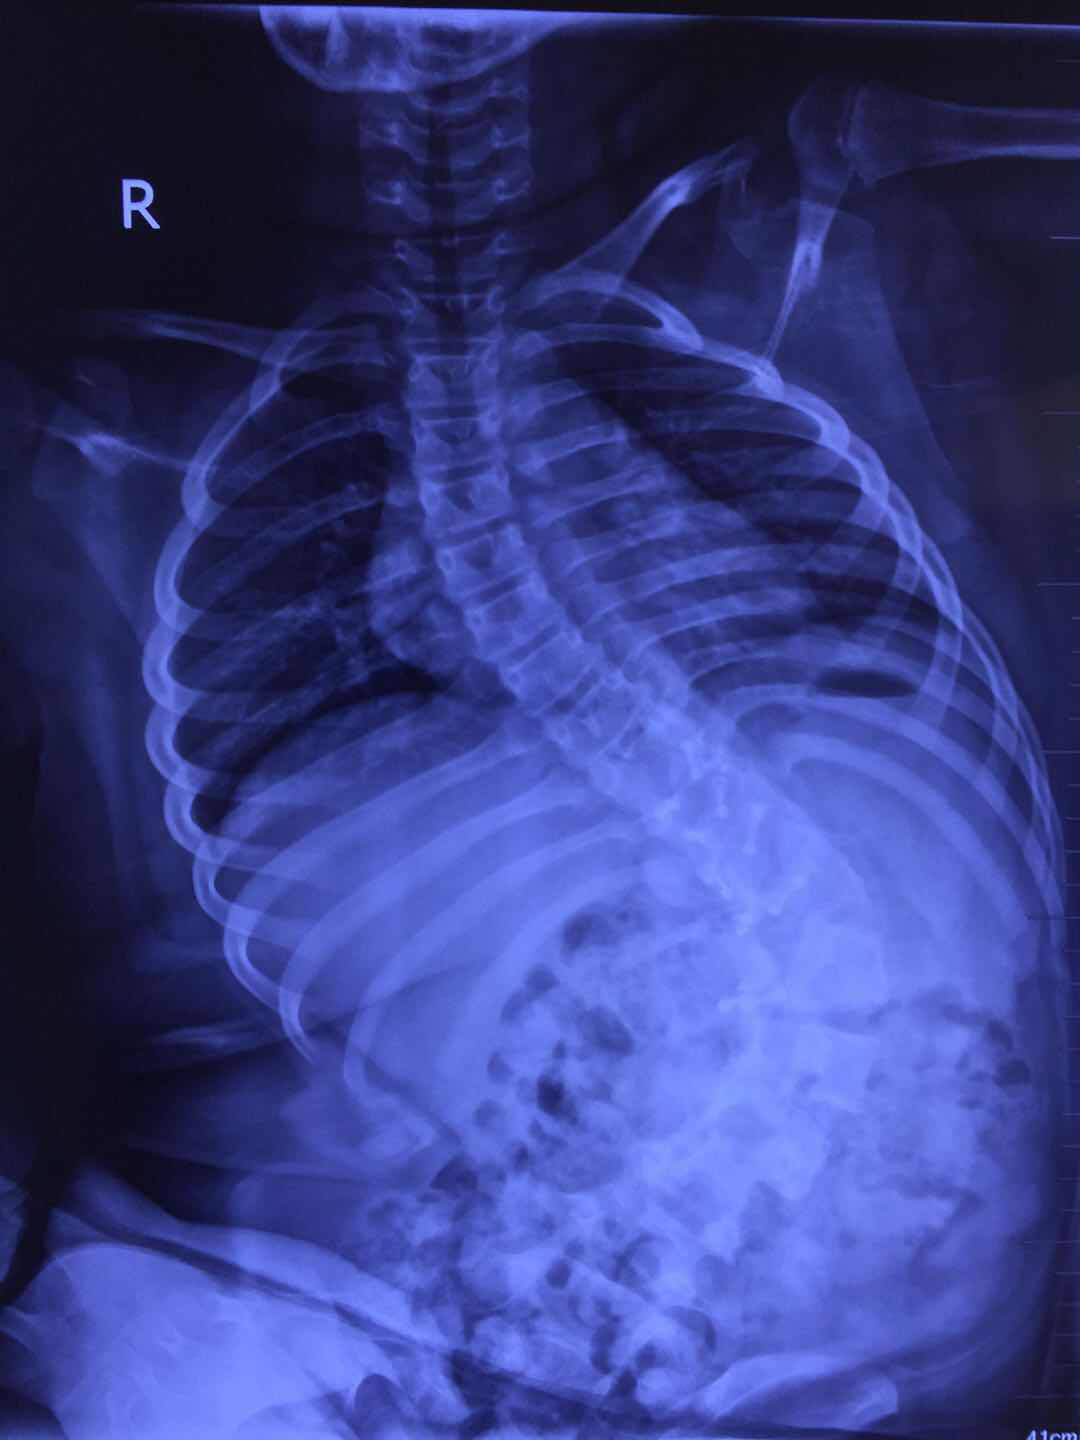

郭晓东教授提供的影像学资料显示,下腰瘫痪后的孩子脊柱弯成了这样。